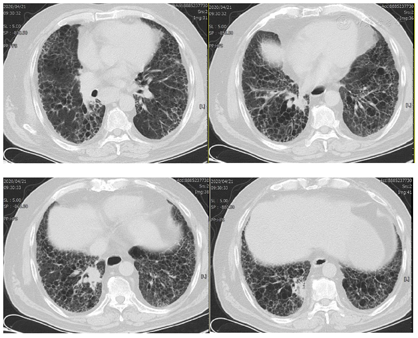

患者经治疗后肿瘤病灶明显缩小(图3,图4,图5,图6,图7,图8),定期于我院随访复查,目前一般情况良好,未见复发及远处转移。

PD-L1是一种跨膜糖蛋白,属于B7家族成员之一,一级结构包括290个氨基酸,亦由胞外区、疏水跨膜及尾部胞浆区组成[2]。有研究发现,PD-L1蛋白广泛表达于活化T淋巴细胞、巨噬细胞、B细胞等免疫细胞,还表达于多种类型的恶性肿瘤细胞表面,比如乳腺癌、胶质瘤、恶性黑色素瘤等[3]。PD-L1与其受体程序性死亡分子1 (PD-1)结合形成PD-1/PD-L1通路,该通路可介导形成机体的免疫抑制微环境,参与肿瘤细胞的免疫逃逸,继而促进肿瘤的发展。研究发现,27%~50%的肺癌患者可表达PD-L1[4,5],Koh等人[6]发现,在肺腺癌组织中PD-L1的阳性表达率为59%,且其阳性表达与患者淋巴结转移、组织分化程度及吸烟有关。有研究结果表明,肺鳞癌组织PD-L1阳性表达明显高于正常肺组织,PD-L1阳性表达与患者pTNM分期、淋巴转移有关,提示PD-L1在肺鳞癌的发生、进展过程中具有重要作用[3]。但目前单独研究PD-L1对肺鳞癌患者预后影响的报道甚少,尤其是伴有肺间质纤维化的肺鳞癌患者的相关研究更少,有待于大规模的临床试验。PD-L1抑制剂虽然可以达到预期的抗肿瘤效果,但这是一个非常复杂的过程,也有发生免疫相关不良事件的风险,包括诱发各种器官的炎症反应[7,8]。目前,其背后的机制仍不清楚,但先前的肺部疾病可能是免疫检查点抑制剂诱发肺炎的一个危险因素[9],所以由于肺炎的风险增加,肺间质纤维化合并肺癌患者接受免疫检查点抑制剂治疗的报道甚少。在以往的研究中,与传统非小细胞肺癌的化疗方案相比,抗PD-1治疗导致重度免疫相关性肺炎的发生率较高,但抗PD-L1治疗则不然[10]。也有研究显示,使用PD-1抑制剂患者3/4级免疫相关性肺炎的发生率仅略高于使用PD-L1抑制剂的患者[11]。此例病人为肺鳞状细胞癌伴肺间质纤维化,肿瘤细胞的PD-L1阳性表达百分比高达78%,因此在GP方案化疗的同时联合应用PD-L1抑制剂度伐利尤单抗,并在化疗与免疫联合治疗5疗程后以度伐利尤单抗单药维持。复查时可见右肺下叶的肿瘤病灶迅速且明显缩小,肺间质纤维化未见进展。患者治疗初期躯干部有散在皮疹出现,经抗过敏治疗后皮疹消失。患者1年半来复查病情稳定,未见复发及除淋巴结以外的其他部位转移,没有报告过除散在皮疹以外的免疫相关不良事件发生,也进一步证实了肺鳞癌病人化疗联合抗PD-L1药物作为一线治疗方案的可行性和安全性,为临床工作中肺鳞癌病人的治疗提供了新的思路。但目前病例数少,有待于大规模的临床试验。我们期望,在不远的未来,免疫治疗可使越来越多的肺癌患者获益。